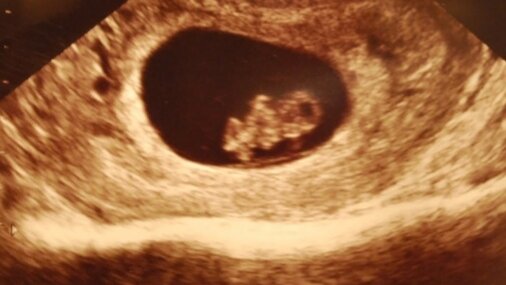

Приблизительно вес малыша 2 г. рост 2,3 см Сроке 8 недель беременности развиваются кости и хрящи, что приводит к росту конечностей. Продолжается развитие сердца. Если вы ожидаете мальчика, на сроке беременности 8 недель у него уже определяются яички. У девочек сейчас формируются яичники, в которых закладываются яйцеклетки. Правда, определить пол плода пока ещё не представляется возможным. 8-я неделя: что происходит с организмом будущей мамы? На этой неделе женщину могут беспокоить все те же ощущения,...